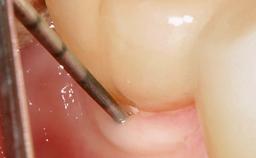

Late Presentation of Peri-Implant Mucositis Requiring Soft-Tissue Augmentation and Esthetic Crown Lengthening at Implant Site 11